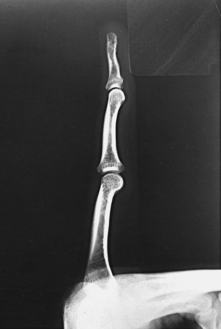

The interphalangeal (IP) articulations between the phalanges are synovial hinge type and allow only flexion and extension (Fig. 4-8). The IP joints are named by location and are differentiated as either proximal interphalangeal (PIP) or distal interphalangeal (DIP), by the digit number, and by right or left hand (e.g., the PIP articulation of the fourth digit of the left hand) (Fig. 4-9, A and B). Because the first digit has only two phalanges, the joint between the two phalanges is simply called the IP joint.

Structures shown: A lateral projection of the affected digit is shown (Figs. 4-24 through 4-27).